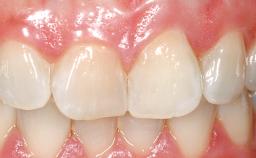

A 30-year-old female patient had lost tooth 21 and was referred to our clinic for consultation and treatment. Due to advanced apical infection, tooth 21 had been extracted two months earlier at another clinic and an acrylic-resin tooth had been bonded to the adjacent teeth. The patient desired implant treatment to avoid any damage to the adjacent natural teeth. While the patient had no history of any systemic disorder, she was a heavy smoker and exhibited medium to advanced periodontitis in the entire jaw. After the initial treatment to achieve a pocket probing depth of less than 4 mm and no bleeding on probing, a decrease in the height of the papillae mesial and distal to the extraction site and overall gingival recession were observed.

Lip Line No exposure of papillae Exposure of papillae Full exposure of mucosa margin

Periodontal Phenotype Low-scalloped, thick Medium-scalloped, medium-thick High-scalloped, thin

Soft Tissue Anatomy Intact Defective